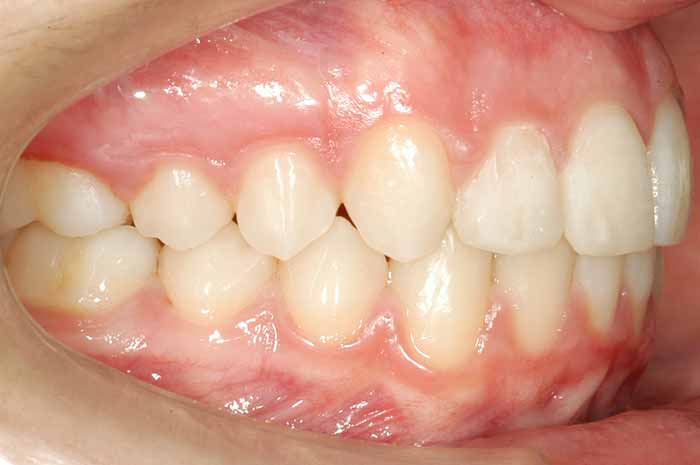

Mordida cruzada anterior

Uno o varios incisivos superiores se situan por detrás de los inferiores, pudiendo alterar el correcto cierre de la boca.

Antes y Después